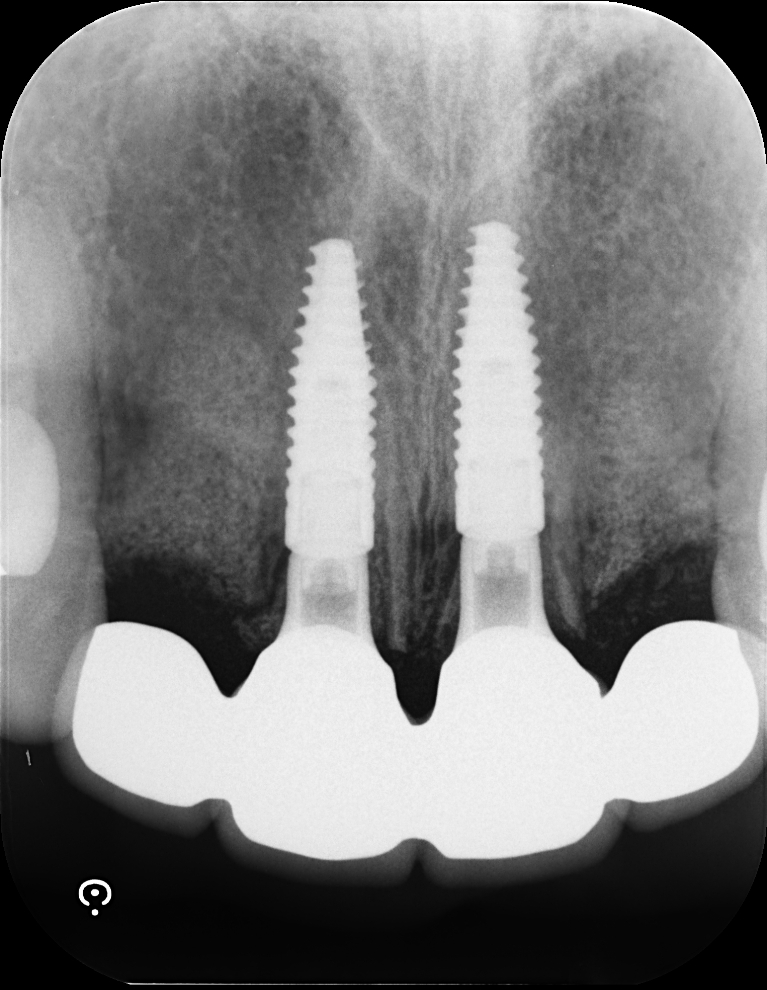

Case4

術前

術中

術後

| 治療名 | GBRとインプラントを行った症例 |

|---|---|

| 治療説明 | インプラントを埋入予定の部位において、骨の吸収が見られたため、インプラント埋入と同時に小規模な骨造成(GBR)を行いました。治癒期間を経て、最終的にセラミックの上部構造を装着し、自然な見た目としっかりとした噛み合わせを回復しました。 |

| 治療回数・期間 | 6ヶ月 |

| 副作用とリスク | インプラント治療は、入れ歯やブリッジに比べて治療期間が長くなる傾向があります。骨造成が必要な場合は、さらに治療期間が延びることがあります。 また、手術後には一時的な違和感や痛み、腫れ、出血などが生じる場合がありますが、通常は2日〜1週間ほどで落ち着きます。 |

| 料金(税込) | GBR〈小規模骨造成〉:110,000円 インプラント一次手術:220,000円 二次手術:55,000円 上部構造〈セラミック〉:165,000円 合計:550,000円 |